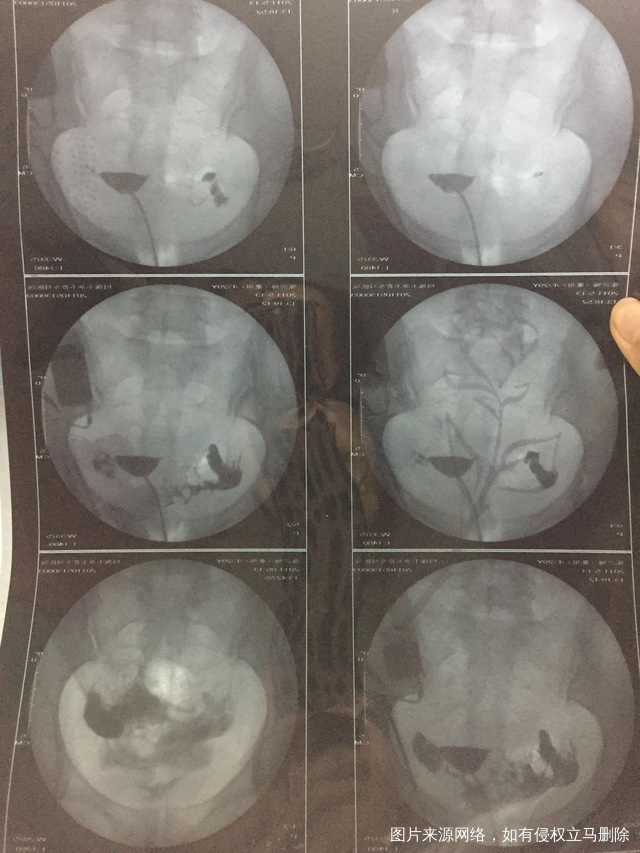

这种必须做手术么还是取了胚胎不是非要做

这个手术不是非得要马上做,需要根据你的年龄、生育计划等来综合评估并权衡利弊后再决定是否需要手术以及什么时候做。如果是做试管通常为了避免输卵管积液及炎症因子逆流至宫腔影响胚胎着床等,会行输卵管结扎等手术,这个手术通常在移植前完成